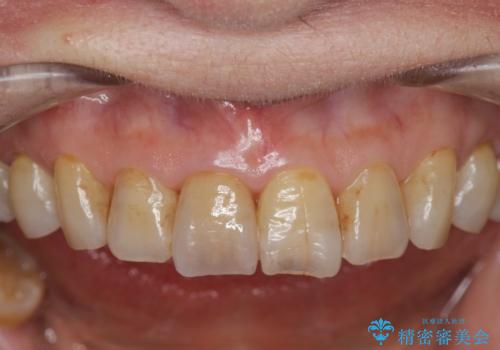

色調の変化が少なく、長期的な予後を見込めるジルコニアクラウンで天然歯を模した審美性の回復を計画します。

当法人でご提案できる最上位クラスのジルコニアクラウンです。